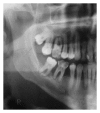

Infections are increasingly considered as potential trigger for carcinogenesis apart from risk factors like alcohol and tobacco. The discussion about human papilloma virus (HPV) in oral squamous cell carcinoma (OSCC) points at a general role of infection for the development of oral carcinomas. Furthermore, first studies describe a correlation between chronic periodontitis and OSCC, thus, characterizing chronic inflammation as being a possible trigger for OSCC. In front of this background, we present four well-documented clinical cases. All patients showed a significant anatomical relation between OSCC and clinical signs of chronic periodontitis. The interindividual differences of the clinical findings lead to different theoretical concepts: two with coincidental appearance of OSCC and chronic periodontitis and two with possible de novo development of OSCC triggered by chronic inflammation. We conclude that the activation of different inflammatory cascades by chronic periodontitis negatively affects mucosa and bone. Furthermore, the inflammatory response has the potential to activate carcinogenesis. Apart from a mere coincidental occurrence, two out of four patients give first clinical hints for a model wherein chronic periodontitis represents a potential risk factor for the development of OSCC.